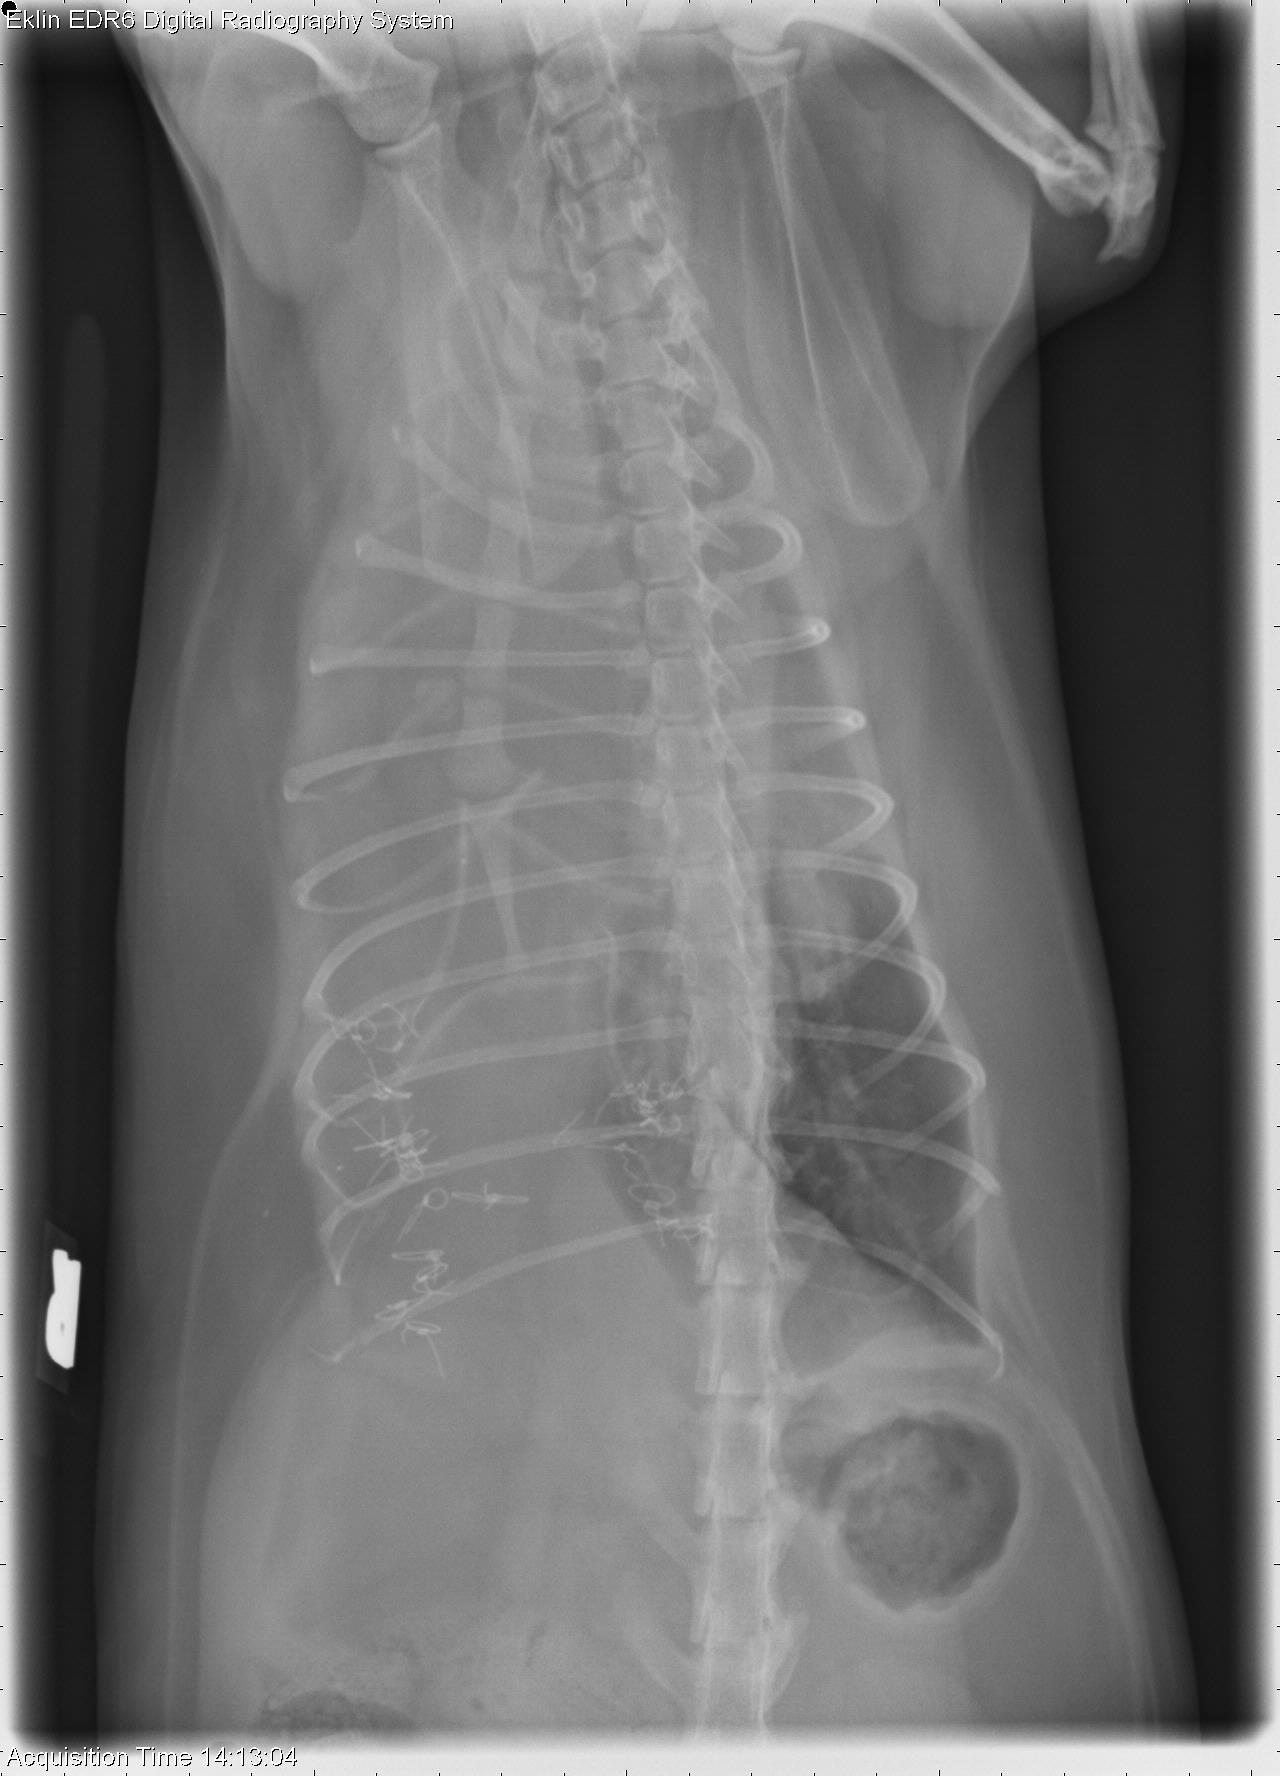

The first case of 2019 is a 7-year-old FS Domestic Medium-hair cat presented with dypsnea. What are your findings?

R LAT Thorax

DV Thorax

VD Thorax

There is a significant increase in fat opacity within the cranioventral thorax. The heart is caudodorsally displaced. The xyphoid is displaced dorsally and multiple metallic sutures are identified within the ventral abdomen. The cardiac silhouette is difficult to visualize on the VD projection due to overlying fat. The right diaphragmatic crus is difficult to visualize on the ventrodorsal projections.

• Diaphragmatic rupture

• Sutures are likely secondary to previous diaphragmatic repair

• A diaphragmatic rupture was confirmed at surgery and was repaired.